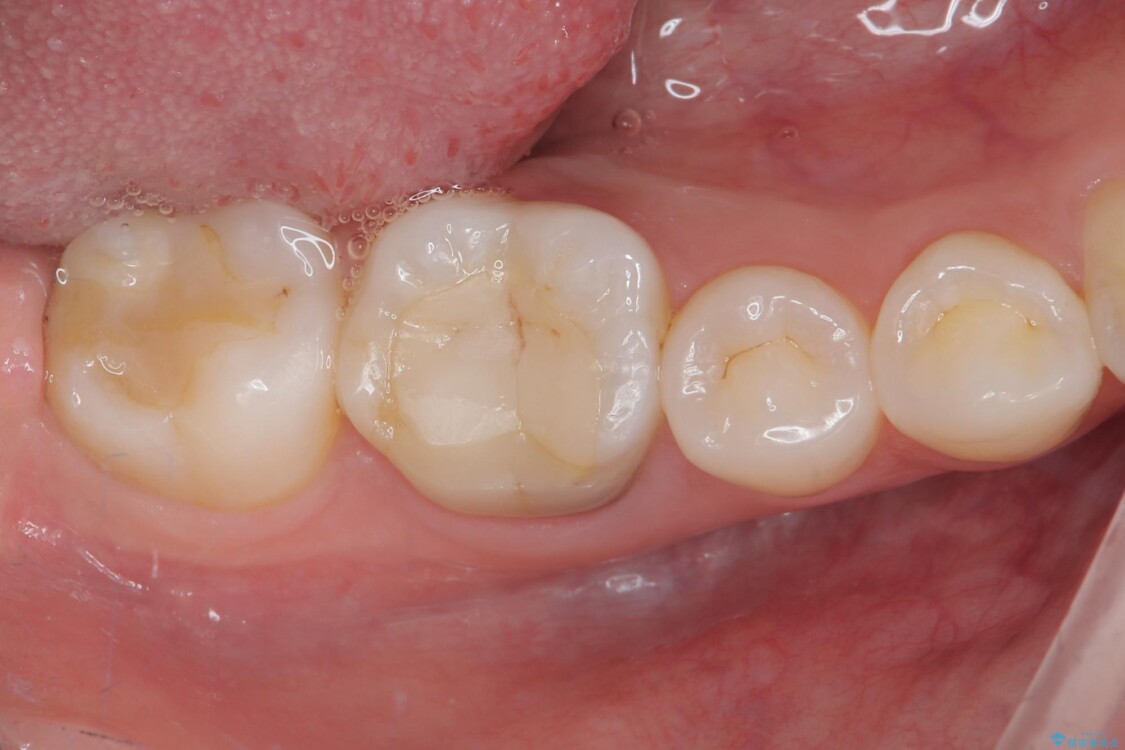

• ラバーダム使用で再感染リスクを抑えた再根管治療+精密な補綴による長期安定を実現 治療後画像